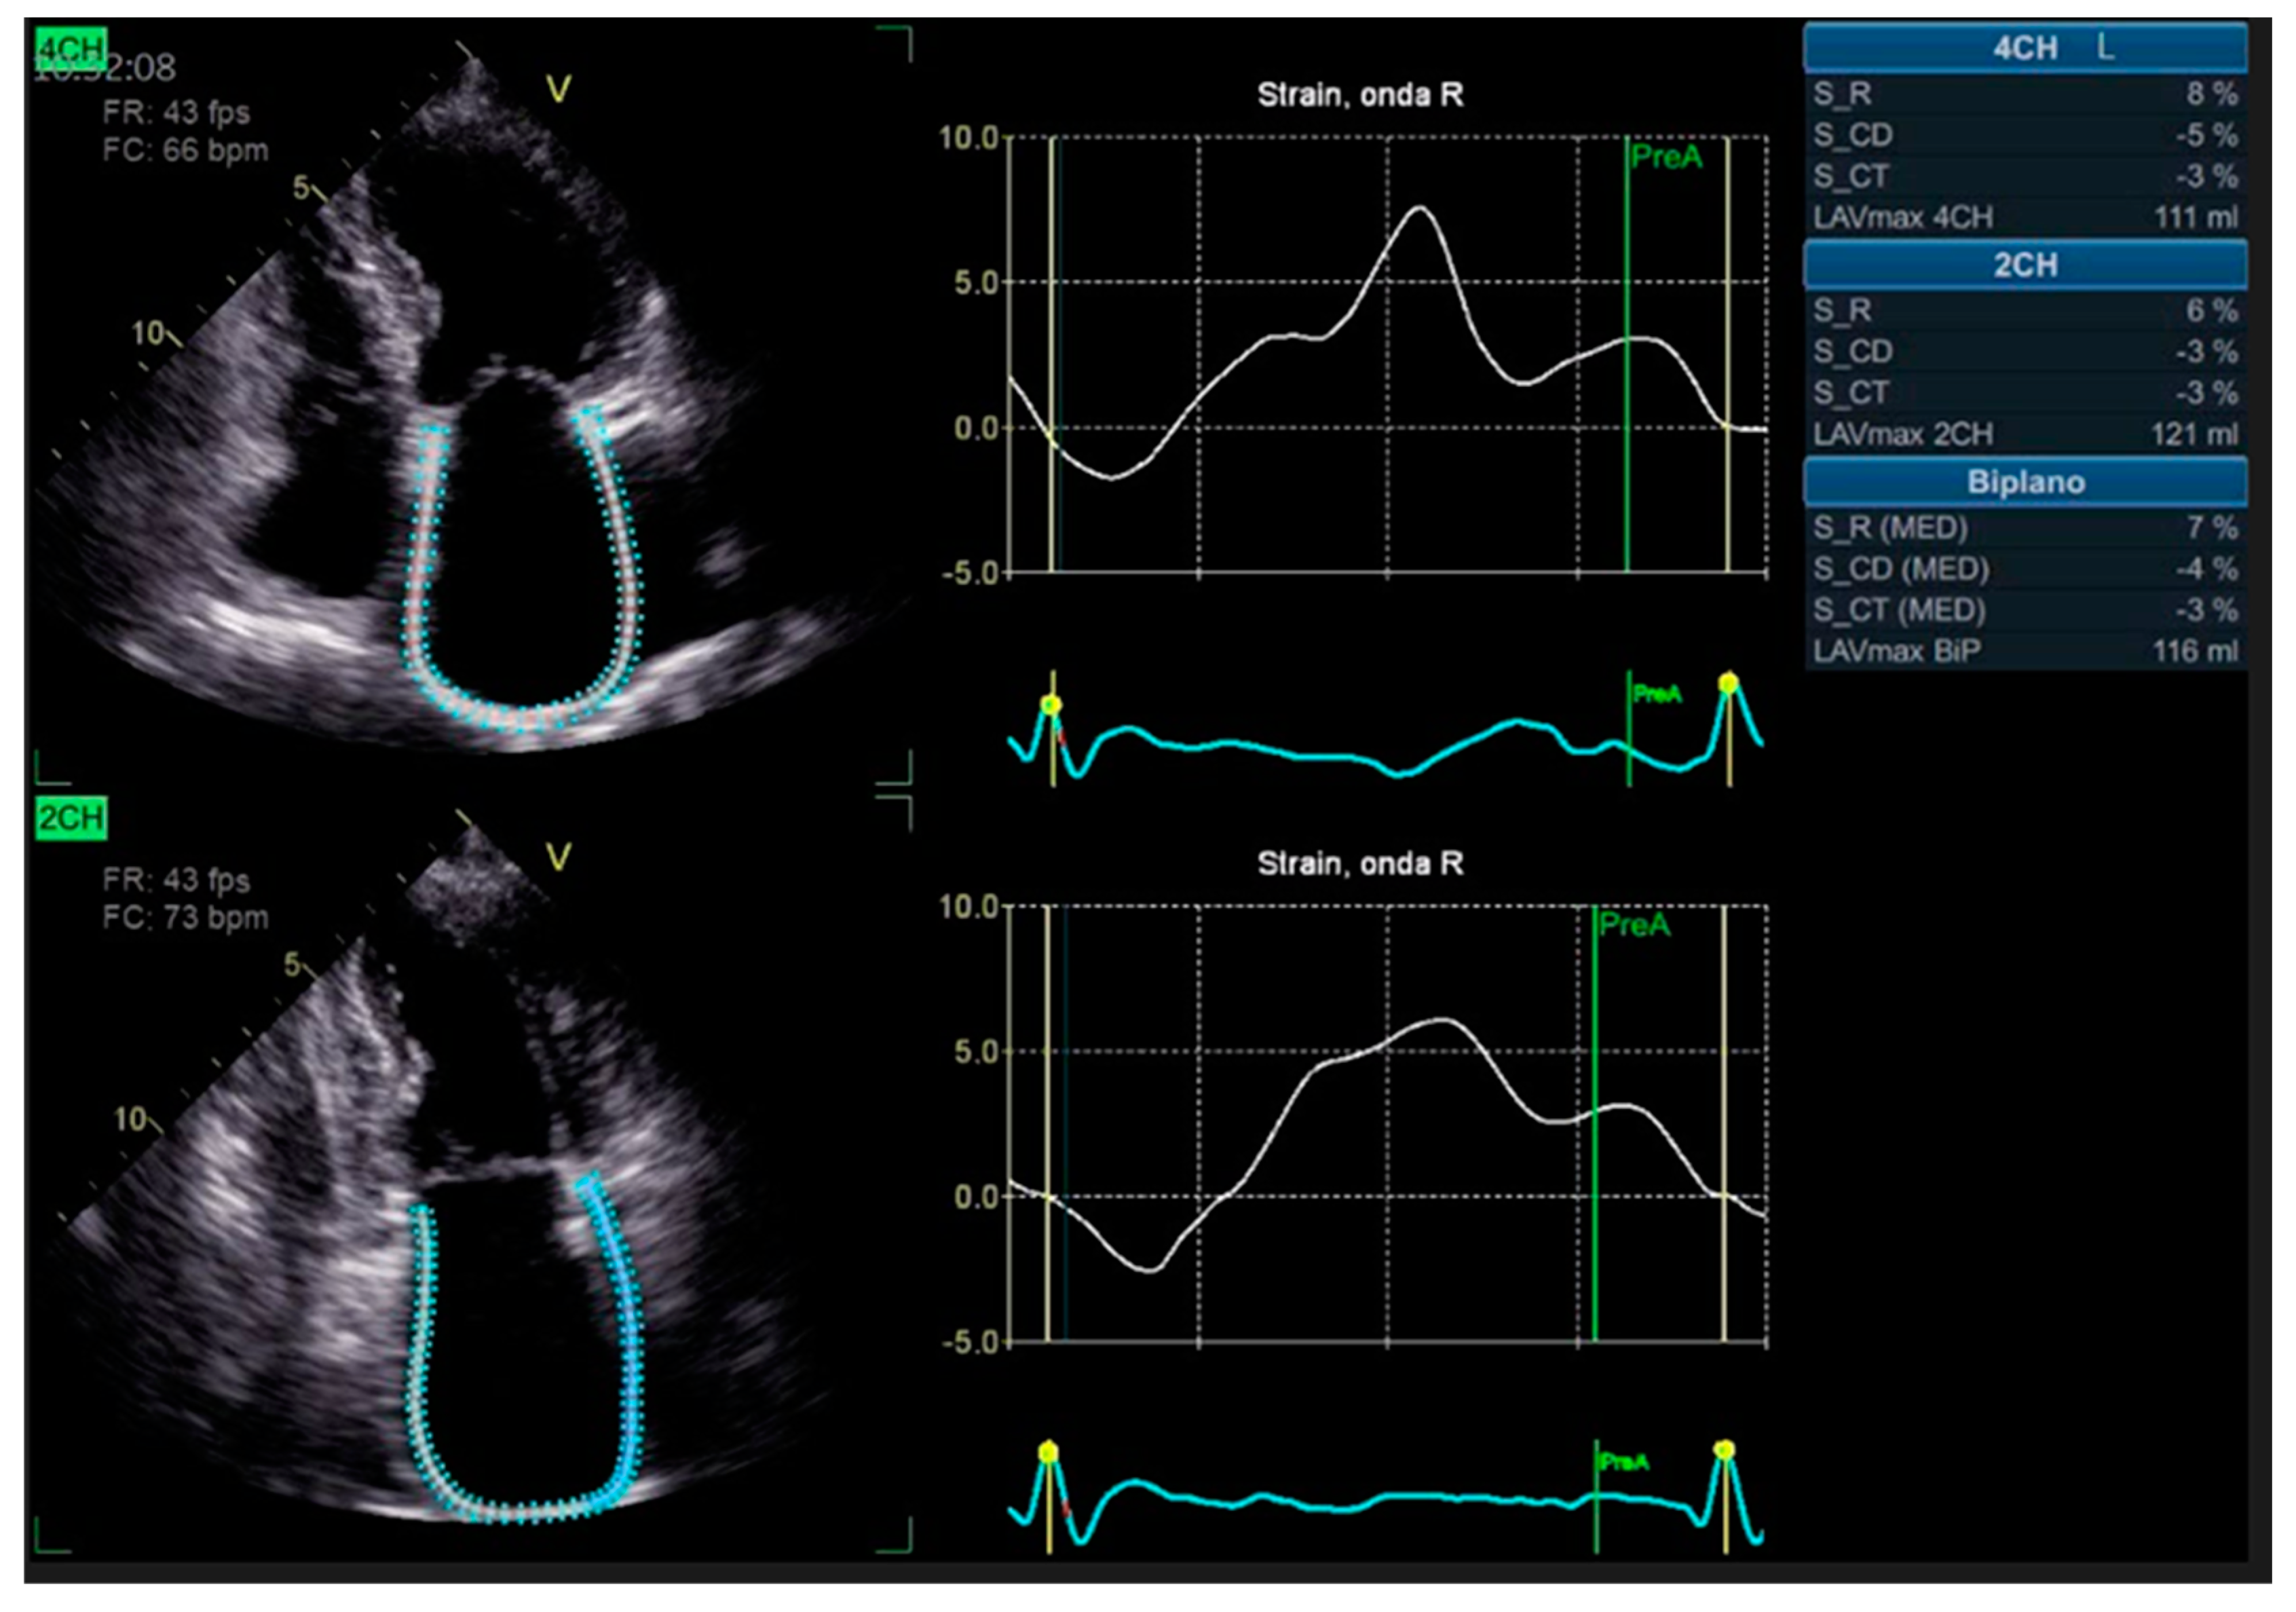

The integration of intravascular ultrasound (IVUS) with ICA reveals approximately 19% more cases of CAV, making it the most sensitive test available for monitoring CAV progression in the clinical setting [55]. However, CCTA has been proposed as an alternative to IVUS for routine follow-up of HT patients due to its superior spatial resolution [56]. In a recent meta-analysis, the sensitivity, specificity, positive predictive value, and negative predictive value of CCTA for detecting CAV were reported as 97%, 81%, 78%, and 97%, respectively [57]. Nevertheless, there is currently no standard method available for the assessment of CAV on CCTA images, and distinguishing CAV from atherosclerotic lesions can be challenging (examples in Figure 2 and Figure 3).

Figure 2. Cardiac computed tomography images showing cardiac allograft vasculopathy grade III according to the International Society for Heart and Lung Classification. Right coronary artery reconstruction with a calcific coronary plaque at the second tract assessed with cardiac computed tomography angiography (right panel) and his orthogonal views (left panel).